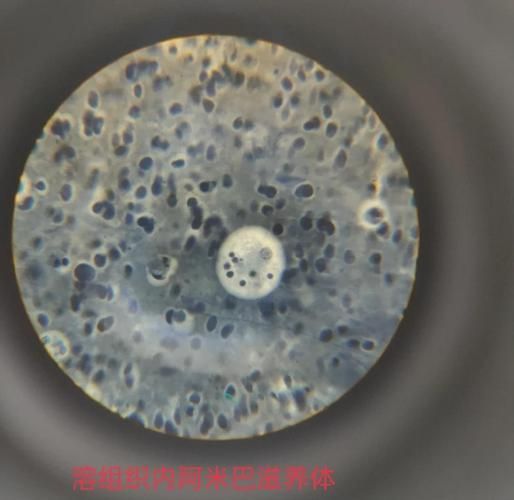

|寄生蟲性| 圓形胞囊,內(nèi)含運(yùn)動性幼蟲,胞囊壁透明,鏡下可見蟲體擺動 |